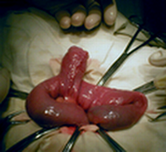

Рис. 1, 2. Дивертикул Меккеля во время операции.